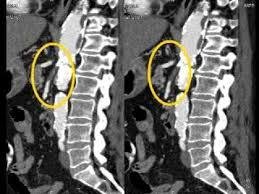

Mesenteric Atherosclerosis

(Intestinal Angina)

- postprandial abdominal pain

- diarrhea

- weight loss

- epigastric bruit

- emaciated

Renal atherosclerosis

- malignant hypertension

- multiple anti-hypertensives

Physical exam

- RUQ or LUQ bruit

- significant hypertension